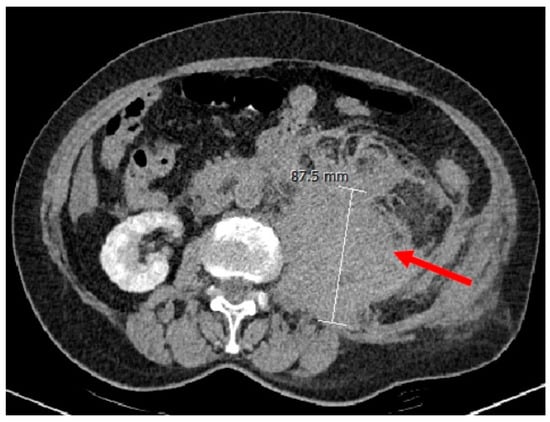

3.1. Case Presentation